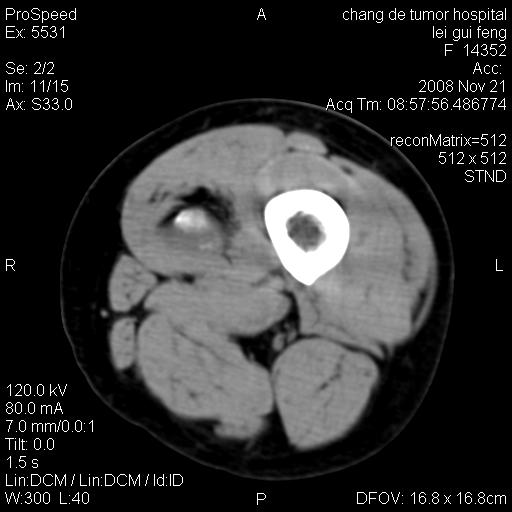

标题: CT16807:女 41 无不适 [打印本页]

标题: CT16807:女 41 无不适

考虑皮样囊肿可能性大

血管瘤可能

血管瘤

血管瘤可能性大!

黏液瘤或表皮杨囊肿

不排除横纹肌肉瘤可能。

血管瘤可能性大或畸胎瘤

考虑脂肪肉瘤

考虑血管瘤可能性大;不排除肉瘤可能。建议行活检。

脂肪肉瘤?

双是软组织肿瘤,病灶内多发钙化,另可见多量脂肪密度影,考虑畸胎瘤,血管瘤,不除外其他